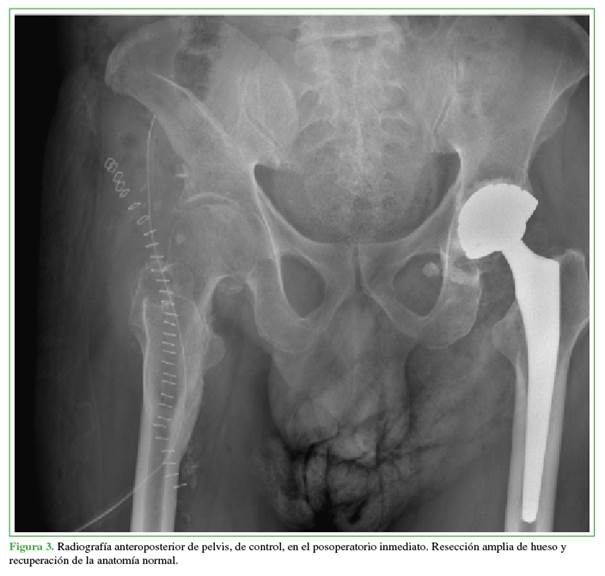

En la cirugía, se identificó una OH grado IV de Brooker con compromiso desde la ceja acetabular hasta el trocánter menor de la cadera derecha, con una marcada vascularización en la lesión. Se realizó un abordaje iliofemoral de la cadera derecha, se exploraron los vasos y el nervio femoral, y se rechazaron hacia la región medial. Luego, se procedió a la disección tanto proximal como distal para localizar ambos focos de osificación, seguida de una osteotomía central. Se resecaron el tercio medio y la región distal, y se realizó una osteotomía de la osificación a nivel del trocánter menor, disecando por planos. Se ubicó la cápsula de la cadera y se efectuó una osteotomía proximal de la osificación, la cual fue retirada en bloque. Se verificaron los arcos de movilidad, que tenían una mejora significativa, y se comprobó la estabilidad de la cadera (Figura 2). La cirugía continuó con aumentación con peróxido de hidrógeno, seguida de un lavado con 3000 cc de solución salina al 0,9%, hemostasia exhaustiva y la aplicación de cera ósea. Se dejaron dos Spongostan® proximales debido al sangrado importante, por lo que fue necesario mantener al paciente bajo observación en la Unidad de Cuidados Intensivos; se administró una transfusión de 5 unidades de glóbulos rojos, 3 unidades de plasma fresco y una aféresis de plaquetas, además de soporte vasopresor.

En el seguimiento radiográfico inmediato y a los tres meses de la cirugía (Figuras 3 y 4), se confirmó la resección completa de la osificación. Clínicamente, al año de la cirugía, el paciente tenía una notable mejora en los arcos de movilidad, con extensión completa y flexión de 110°. Además, logró retomar la marcha con la ayuda de un caminador. Continúa con terapia física y fortalecimiento del cuádriceps bajo la supervisión de Fisiatría, sin dolor ni complicaciones adicionales hasta la fecha.